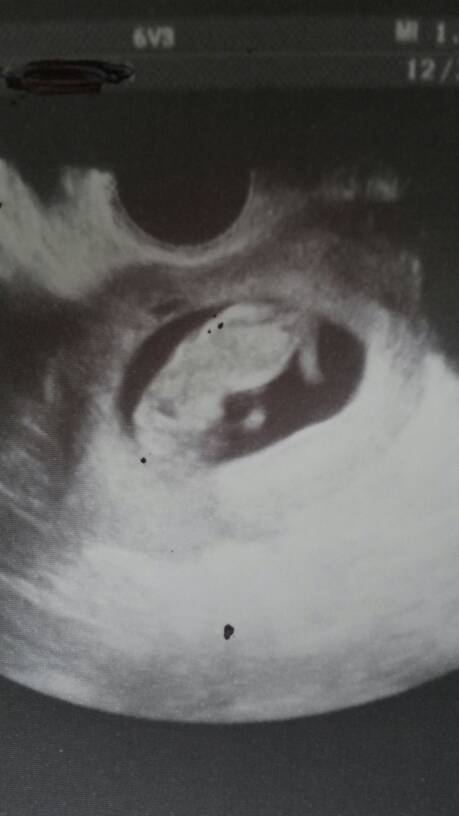

Ja juz po wizycie. Wszystko dobrze. Zdjęcie mam kijowe bo za 2 tyg mam i tak pretenalne to się naogladam. Tak tylko sprawdził czy żyje, pokazał lapki, nóżki, serduszko bijące, nie robił pomiarów ani nic. Poprosiłam o zdjatko jakieś to mi pyknal takie średnie ujęcie ale ja widziałam prawdziwego małego czlowieczka :)

Kruczyca ja też tam widzę małego czlowieczka. Super :)